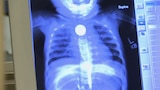

3. Un parásito me come la cara

Un viajero regresa de un viaje a Sudamérica con una misteriosa infección devoran...